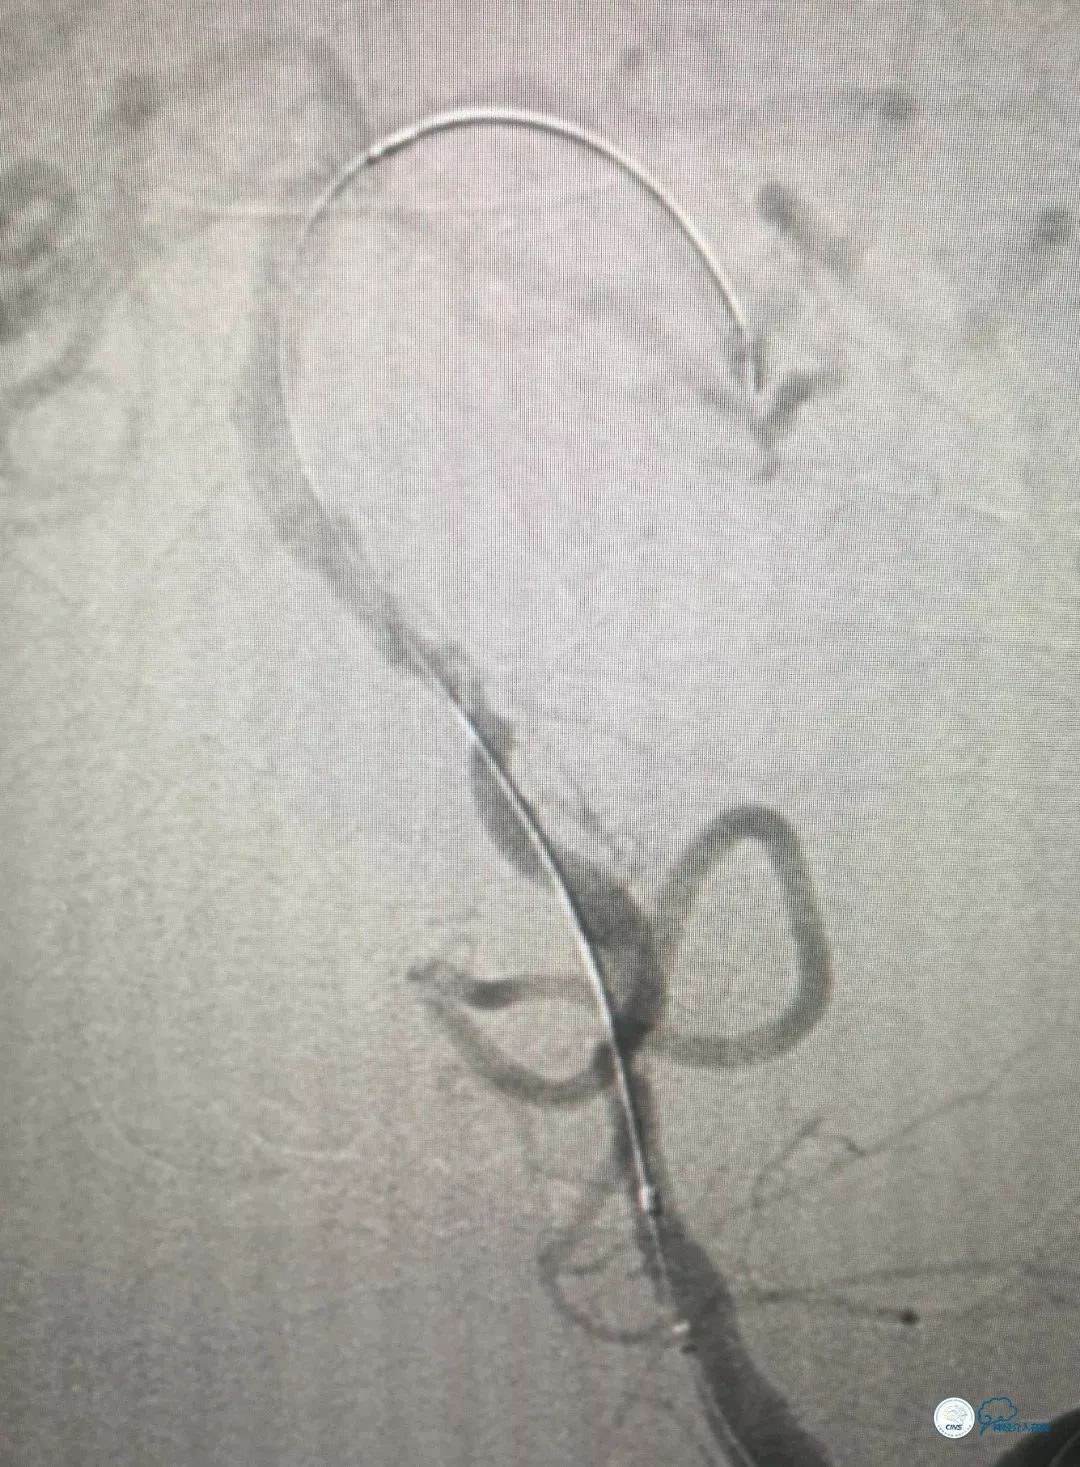

全麻下右侧股动脉穿刺置入6F动脉鞘, 6F导引导管至左椎动脉V2段远端,术前造影示左椎动脉V4段与基底动脉交界处重度狭窄(图8)。

图8